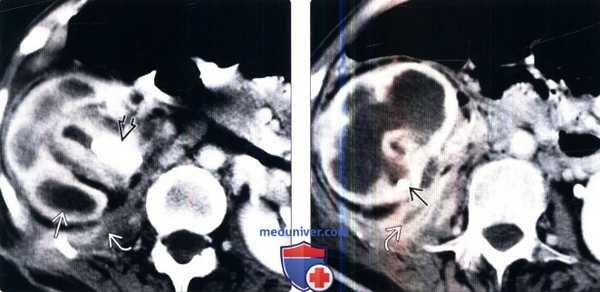

(Левый) На рисунке показан ксантогранулематозный пиелонефрит (КГПН) в нижнем полюсе почки с продолжительной обструкцией лоханочно-мочеточникового сегмента крупным коралловидным конкрементом, что привело к замещению паренхимы почки скоплениями «пенистых» макрофагов.

(Правый) На поперечном УЗ срезе с цветовой допплерографией визуализируется расширенная чашечно-лоханочная система со взвесью и обструкцией конкрементом пузырно-мочеточникового сегмента. Паренхима замещена кистозными образованиями, содержащими взвесь. Обратите внимание на отсутствие васкуляризации в области предположительного расположения паренхимы почки. (Левый) На двух ультразвуковых срезах у другого пациента визуализируются кистозные образования в паренхиме почки кнаружи от конкрементов (обозначены метками) в центральном отделе лоханки. При цветовой допплерографии визуализируется артефакт мерцания от конкрементов.

(Правый) На аксиальном КТ срезе с контрастированием визуализируется крупный центральный конкремент, практически полное замещение паренхимы скоплениями кист, а также абсцесс со свищевым ходом в прилежащую брюшную стенку. Разрастание околопочечной клетчатки у данного пациента с кахексией является реакцией на хроническое воспаление.